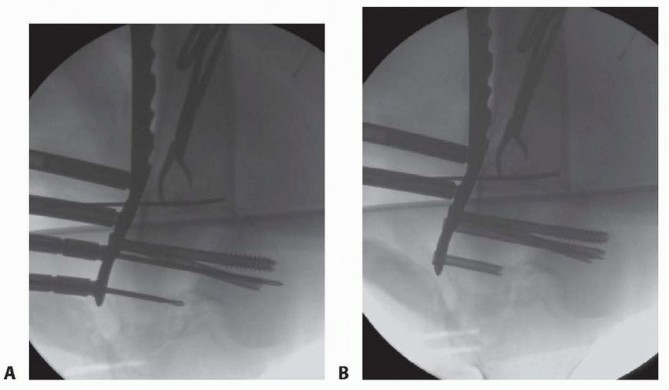

--- TECH FIG 6 • A,B. Patient seen in FIG 15C,D, with the guidewire now pulled back and an appropriately sized screw placed. Once the AP position is obtained, the plate is stabilized proximally. The plate should be temporarily stabilized to the bone proximally. Before the temporary stabilization, the length and rotation must be checked. Ideally, if the temporary fixator is in place, these two parameters have been maintained during the course of the operation. If no screw targeting guide is present, a percutaneous provisional fixation pin can be used to stabilize the plate. If a targeting guide is used, then a soft tissue guide for the most proximal hole is placed percutaneously and a drill bit or guidewire is used to stabilize the plate. The variable-angle locking plates also have proximal shaft targeting devices; however, variable locking trajectories can only be accomplished outside the targeting device and can be cumbersome. Generally, variable-angle locking is not necessary in the shaft and locking screws collinear with the hole can be placed through the targeting device. ( FIG 11E, red arrows showing perpendicular nature of locking screws; FIG 11F, variable-angle locking screws in the shaft are useful in cases where there is a preexisting hip replacement with a femoral component.) Again, the flexion-extension reduction should be checked. This procedure creates our “box” construct, which aids in the placement of screws through the targeting device (if used) and in temporary stabilization of the fracture construct. ### Screw Placement If the intercondylar split is going to be stabilized by screws through the plate, partially threaded screws or overdrilled fully threaded screws should be used first to provide interfragmentary compression. Specially designed conical screws for certain systems exist, or large partially threaded screws can be used ( >4.5 mm). This also compresses the plate to the bone. Once the articular injury is addressed, at least two additional locking screws should be placed into the distal segment to secure the plate and the alignment. The trajectory of distal locking screws can be assessed on the notch view to ensure that penetration through the intercondylar notch does not occur ( TECH FIG 6; see FIG 15C for C-arm setup and position for this image). Before placing the locking screws, the length, rotation, and alignment must be checked again if no fixator or distractor is in place holding the fracture alignment. The plate can be locked to the distal segment and then used to manipulate the distal segment relative to the shaft for the flexion-extension reduction. This, however, is predicated on proper distal alignment of the plate. Otherwise, once the plate is fixed to the distal segment in a malposition and the fracture reduced, the plate may be anterior or posterior on the shaft. The distal screws in a variable-angle locking plate are noncircular to allow for the variable-angle locking mechanism. Screws can be placed directly collinear or with a “variability” of 15 degrees in any direction depending on the system used (see FIG 11D, square outline). ### Attaching the Distal Segment to the Shaft The distal segment is now fixed and can be attached to the shaft. If there is malalignment in the coronal plane but the sagittal plane alignment is reduced, the shaft can be “pulled” to the plate by means of various threaded devices or a nonlocking screw that can be placed freehand under fluoroscopic guidance or through a targeting jig ( TECH FIG 7). ### Placement of Additional Screws Once proper reduction of the fracture is temporarily achieved and the plate is in proper position, additional screws can be placed. If the targeting screw guide is used, percutaneous locking screws can be placed through the soft tissue drill or screw guides ( TECH FIG 8A-C). If no targeting guide is available, fluoroscopic guidance and a percutaneous method can be used freehand. 484

### TECH FIG 12 • A. Visualization of the joint for articular reduction. B. C-arm image of reduction forceps holding the intercondylar split reduced. C,D. Clinical photographs with forceps followed by guidewires for screw placement. E,F. Lateral views showing pins and wires outside the zone for either plate application or intramedullary nail. The anterior and posterior placement of the pins is seen. (continued) A reduction forceps is placed anteriorly to hold the reduction ( TECH FIG 12B). Temporary Kirschner wires or guidewires from a cannulated system can be placed for additional stability ( TECH FIG 12C,D). All clamps, Kirschner wires, or guidewires should be placed outside the zone of plate application ( TECH FIG 12E,F). 488